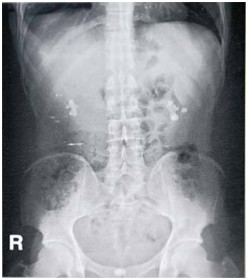

【影像诊断模拟题】患者,男性,32岁,腰痛1小时入院,腹平片提示

2022-04-24